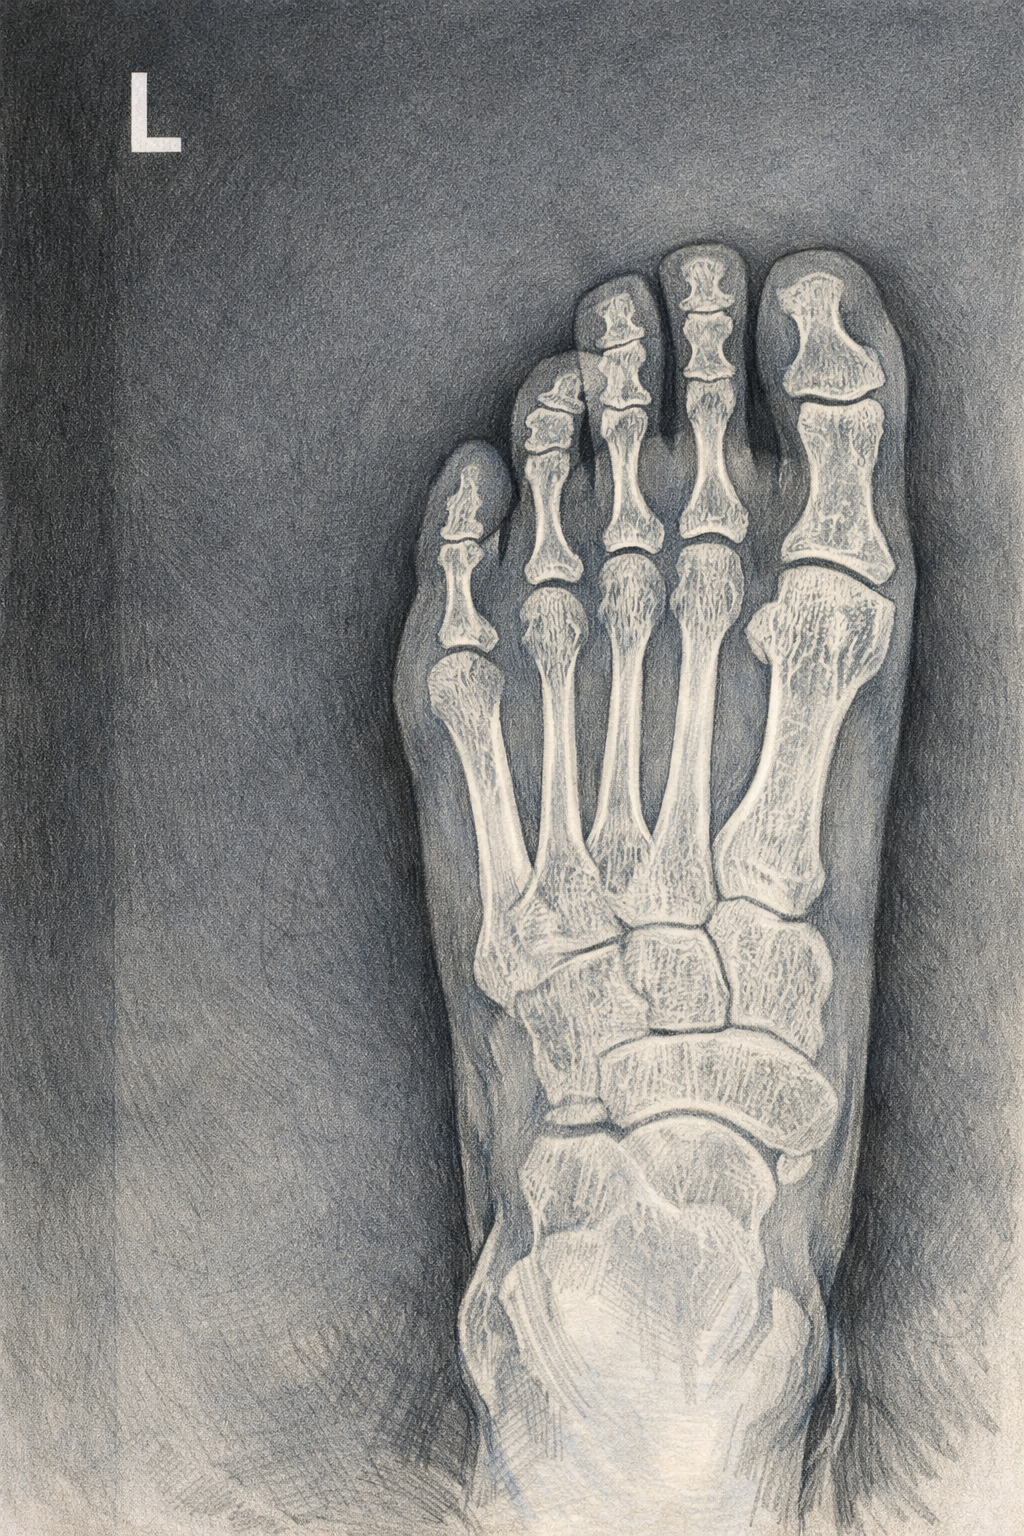

하지만 나는 어린이가 아닌 이미 30대의 신체를 가진 사람. 대부분의 시간을 책상에 앉아 보내다가 갑자기 활동적인 움직임을 많이 하다 보니 몸을 어떻게 관리하거나 움직여야 하는지 몰랐고, 그러다 집에서 새끼발가락을 철제 옷걸이에 찧어 미세골절 진단을 받았다. 이 부분은 나름(?) 부끄러운 포인트인데, 운동하다가 골절이 온 것이 아니라 집에서 까불다가 다친 거였기 때문이다.

그 뒤 4주간 훈련을 쉬었다. 의지가 활활 불타는 찰나에 당한(?) 부상이라니. 그것도 내 몸의 가장 가장자리에 있는 (줄 알았던) 새끼발가락 때문에 가장 중요하다고 여기는 축구 훈련을 쉬어야 했던 거다. 매일 물리치료를 받으러 다녔다. 인생 처음 당해본(?) 미세골절의 심각성을 몰랐던 나는 ‘언제 다시 축구할 수 있나요?’를 끈질기게 물었다. 하지만 몸의 회복에는 분명한 시간이 필요하다는 사실. 최소 1개월은 무조건 쉬어야 하고, 완치되려면 적어도 6개월 이상은 걸린다고 했다.